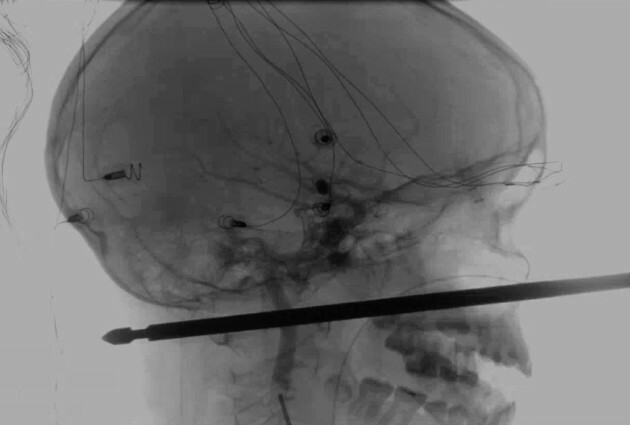

A 10-YEAR-OLD Missouri boy is recovering after he was attacked by insects and tumbled from a tree, landing on a meat skewer that penetrated his skull from his face to the back of his head. But miraculously, that’s where Xavier Cunningham’s bad luck ended. The skewer had completely missed Xavier’s eye, brain, spinal cord and major blood vessels, Xavier’s harrowing experience began Saturday afternoon when yellow jackets attacked him in a treehouse at his home in Harrisonville, about 56 kilometres south of Kansas City. He fell to the ground and started to scream. His mother, Gabrielle Miller, ran to help him. His skull was pierced from front-to-back with half a foot of skewer still sticking out of his face. Miller tried to reassure her son, who told her “I’m dying, Mom” as they rushed to the hospital. He eventually was transferred to the University of Kansas Hospital, where endovascular neurosurgery director Koji Ebersole evaluated the wound.

“You couldn’t draw it up any better,” Ebersole said. “It was one in a million for it to pass 5 or 6 inches through the front of the face to the back and not have hit these things.”There was no active bleeding, allowing the hospital time to get personnel in place for a removal surgery on Sunday morning that was complicated by the fact that the skewer wasn’t round. Because it was square, with sharp edges, it would have to come out perfectly straight. Twisting it could cause additional severe injury.“Miraculous” would be an appropriate word to describe what happened, Ebersole said. Doctors think Xavier could recover completely.“I have not seen anything passed to that depth in a situation that was survivable, let alone one where we think the recovery will be near complete if not complete,” he said.